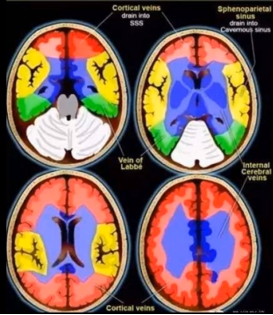

(3)静脉性脑梗死

MRI 表现与硬膜窦内血栓、静脉回流受阻造成的继发性脑实质改变有关:

脑实质改变包括水肿、出血灶。

脑白质(灰白质交界)出血。

DWI 表现不尽相同。

不同血管分布。

如下图可见案例:静脉性脑梗死与动脉性脑梗死对比

(上下滑动查看全部图片)

表:静脉性脑梗死与动脉性脑梗死对比